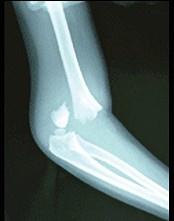

图示骨折,最易损伤 ( )A、肱动、静脉B、桡神经C、肱三头肌D、肌皮神经E、肱二头肌

问题 图示骨折,最易损伤 ( )

选项 A、肱动、静脉 B、桡神经 C、肱三头肌 D、肌皮神经 E、肱二头肌

答案 A